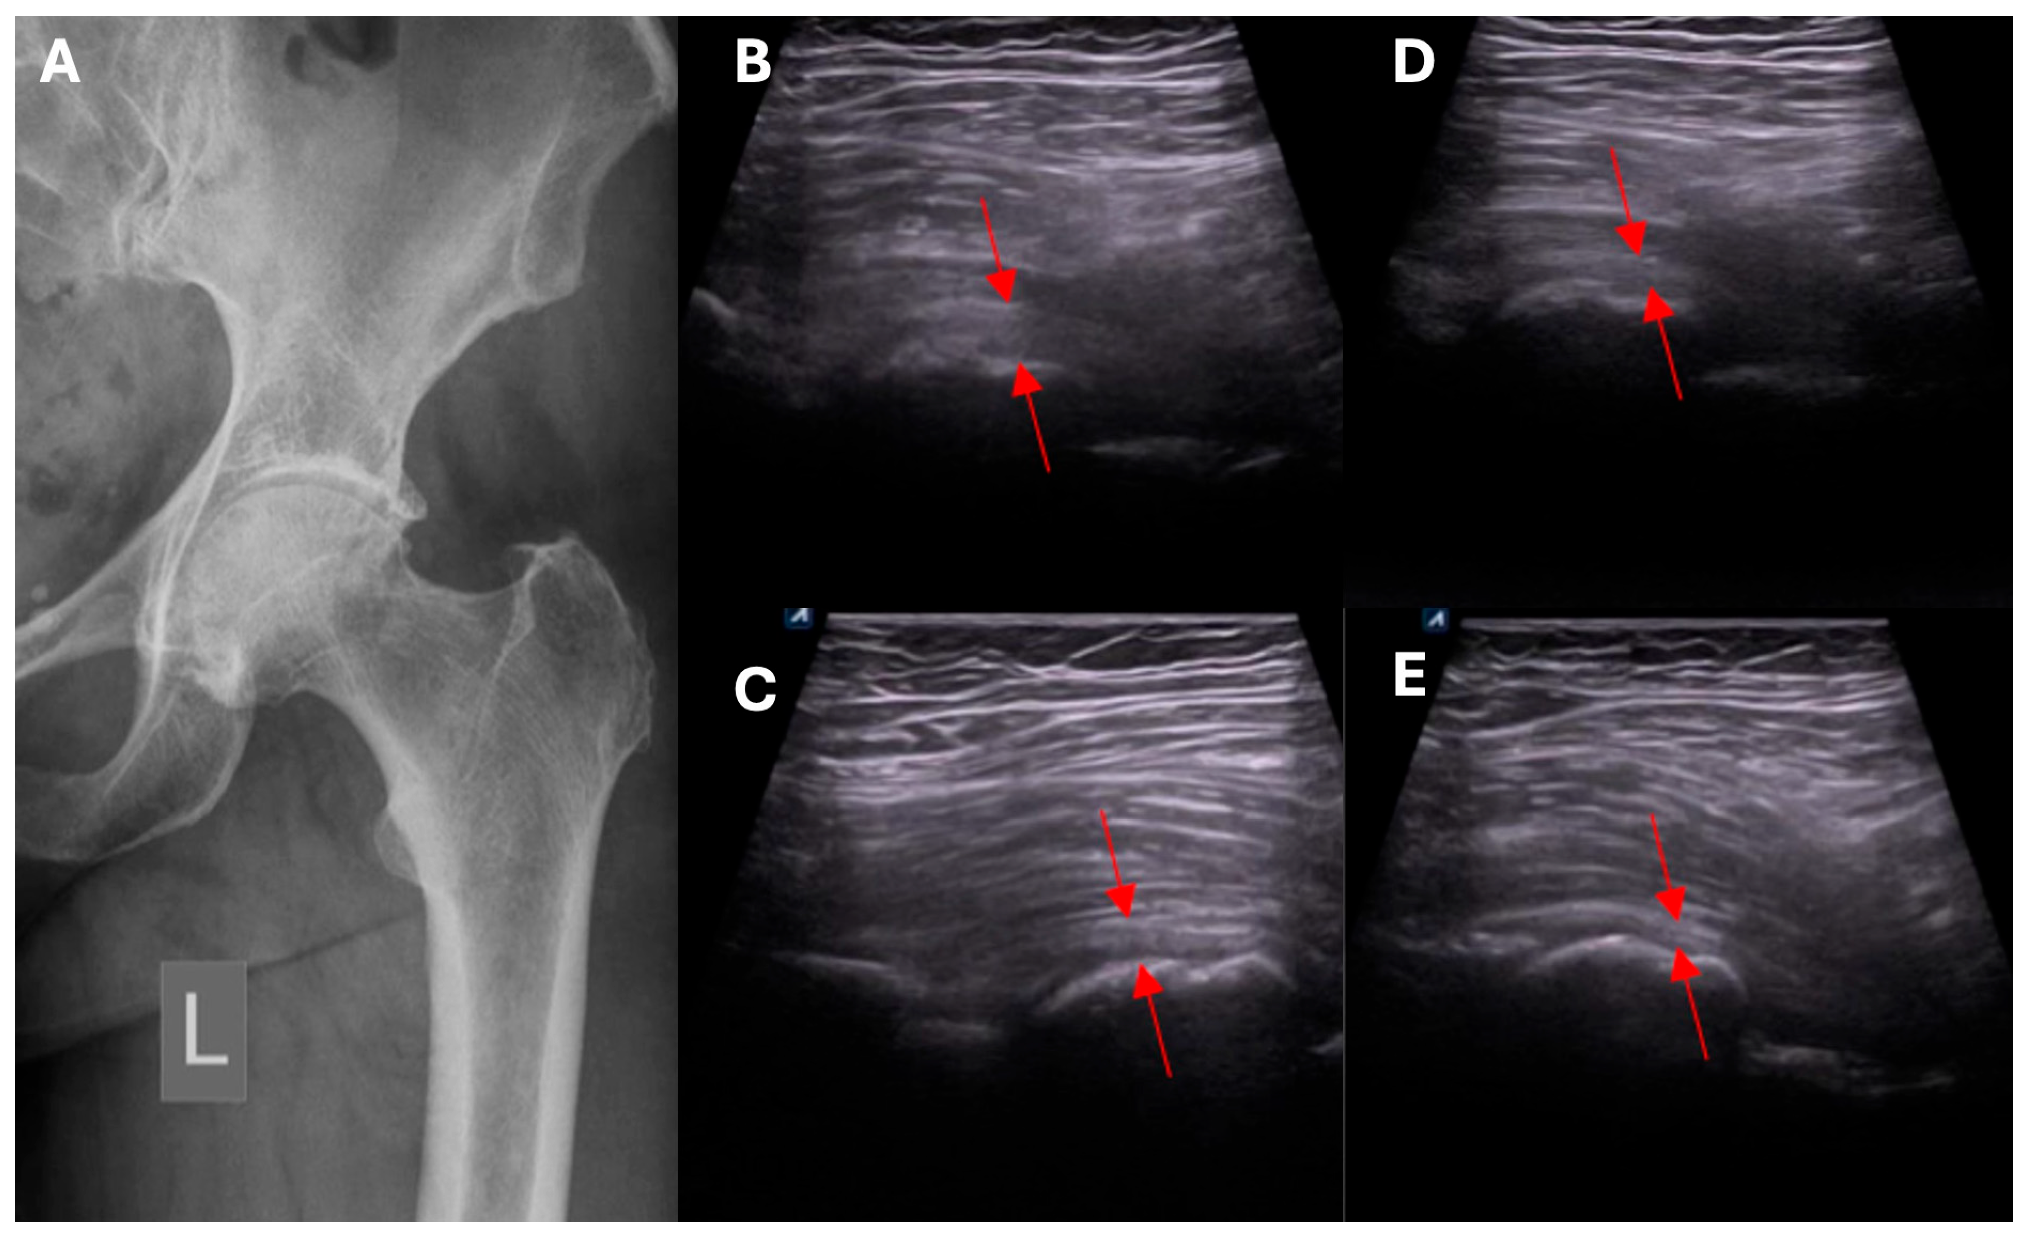

- Ultrasound assessment of hip morphology, and radiologic imaging with MRI where necessary.

- Clinical and ultrasound assessment to identify local pathological mechanisms underlying symptomatic HOA.

- Exclusion/confirmation of intracapsular and extracapsular inflammation based on ultrasound imaging.

- Clinical and ultrasound assessment of the intracapsular, extracapsular, anterior, anteromedial, lateral, and posterolateral aspect of the hip.

- Assessment of capsular adhesion thickness—ultrasonographic evaluation was performed with the probe positioned transversely, allowing for precise visualization of adhesions. The most common location of adhesions was in the anterolateral complex, with less frequent occurrences in the medial complex.